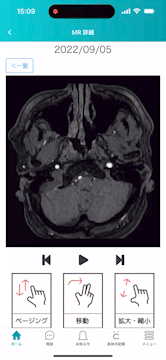

そのような背景を受け、『CARADA健診サポートパック』では本機能を追加します。本機能は、健康診断にて撮影したX線などの画像データを受診者専用アプリ『CARADA 健診サポート』にて閲覧可能とするものです。アプリ上の画像データは、医用画像の共通規格であるDICOM※4形式で表示され、受診者は医療用の高解像度のデータを、角度を変えたり、拡大・縮小しながらスマートフォンで簡単に確認できます。